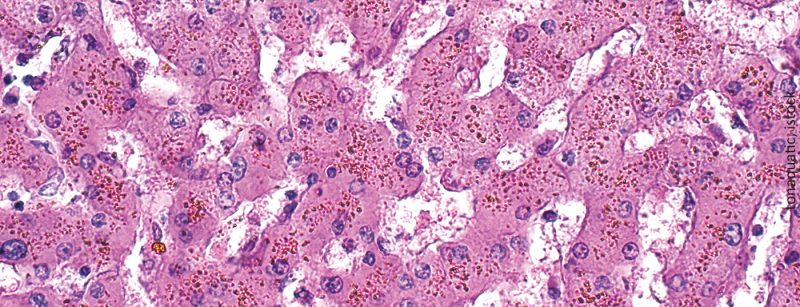

• Eisenüberladung

Pathophysiologie und Klinik

Eine Eisenüberladung ist eine unvermeidliche und potenziell lebensbedrohliche Folge multipler Transfusionen von Erythrozytenkonzentraten. Da die klinischen Manifestationen unspezifisch sind und sich in der Regel langsam entwickeln, wird diese Komplikation häufig...…